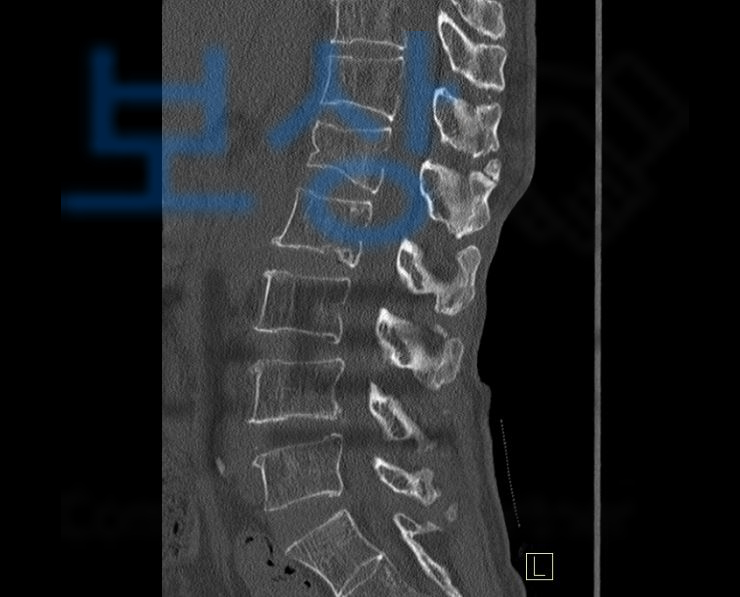

그런데 그 이후로멀쩡하던 허리에 통증이 시작되었고 척추 전문 병원에 방문하여 정밀검사를 받아본 결과

L1 부위 즉 요추의 압박골절

진단받았습니다. 주치의께서 몇 주간의 안정을 말하여 정말정말 조심했지만 여전히 허리의 통증은 가시지 않았는데요, 먼저 견주에게 손해배상을 청구할 수 있습니다. 다행히 견주는 배상책임보험에 가입되어 있었고 보험접수를 하여 보험 처리를 진행하게 되었는데요, 손해 배상의 합의금 계산을 위해서는